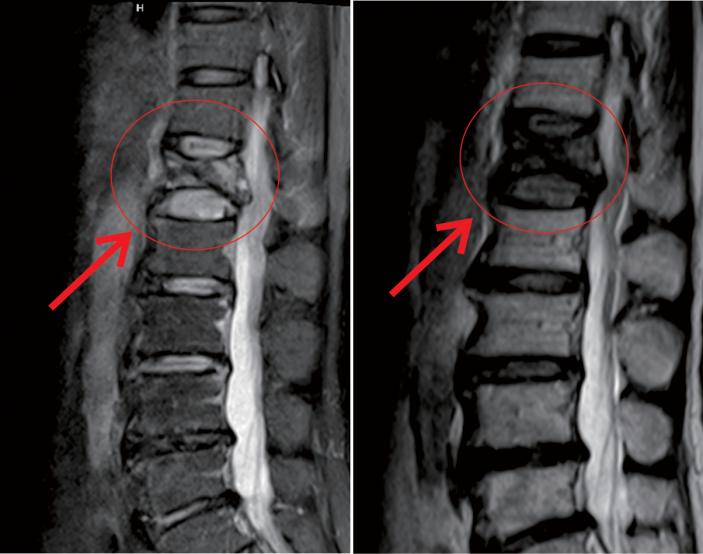

△術前MR顯示,第一腰椎壓縮性骨折

△術後,病變的椎體迅速恢複了功能